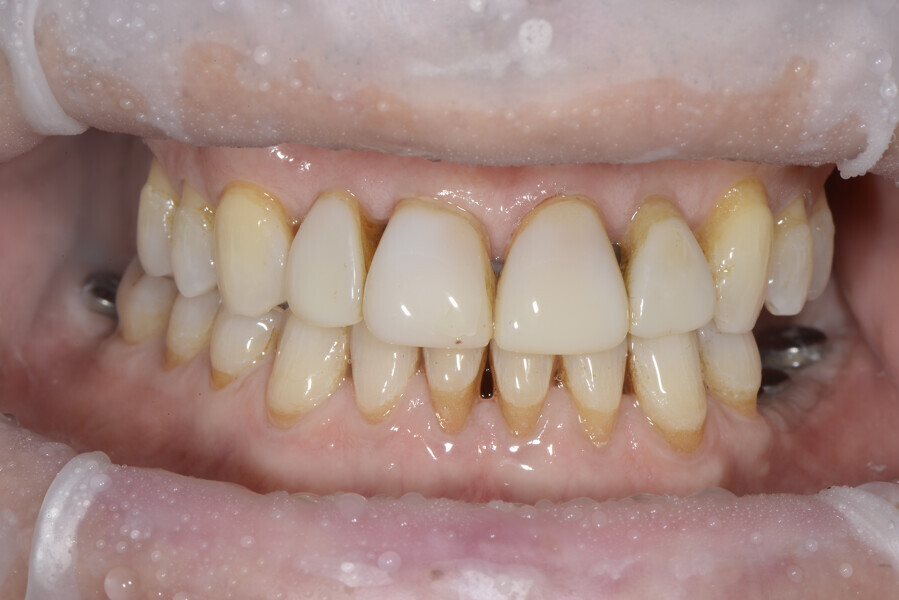

The 58-year-old patient wished to improve his oral aesthetics and function, complaining of mobility of the posterior teeth and wear of the anterior teeth. After data collection, a very complex situation was identified (Figs. 11–13):

1. severe periodontitis with poor prognosis of some teeth;

2. anterior crossbite;

3. severe wear mainly of the anterior teeth and compensatory eruption;38

4. atypical swallowing and lower posture of the tongue at rest;

5. masticatory dysfunction during the mastication test; and

6. no significant signs of temporomandibular disorder.